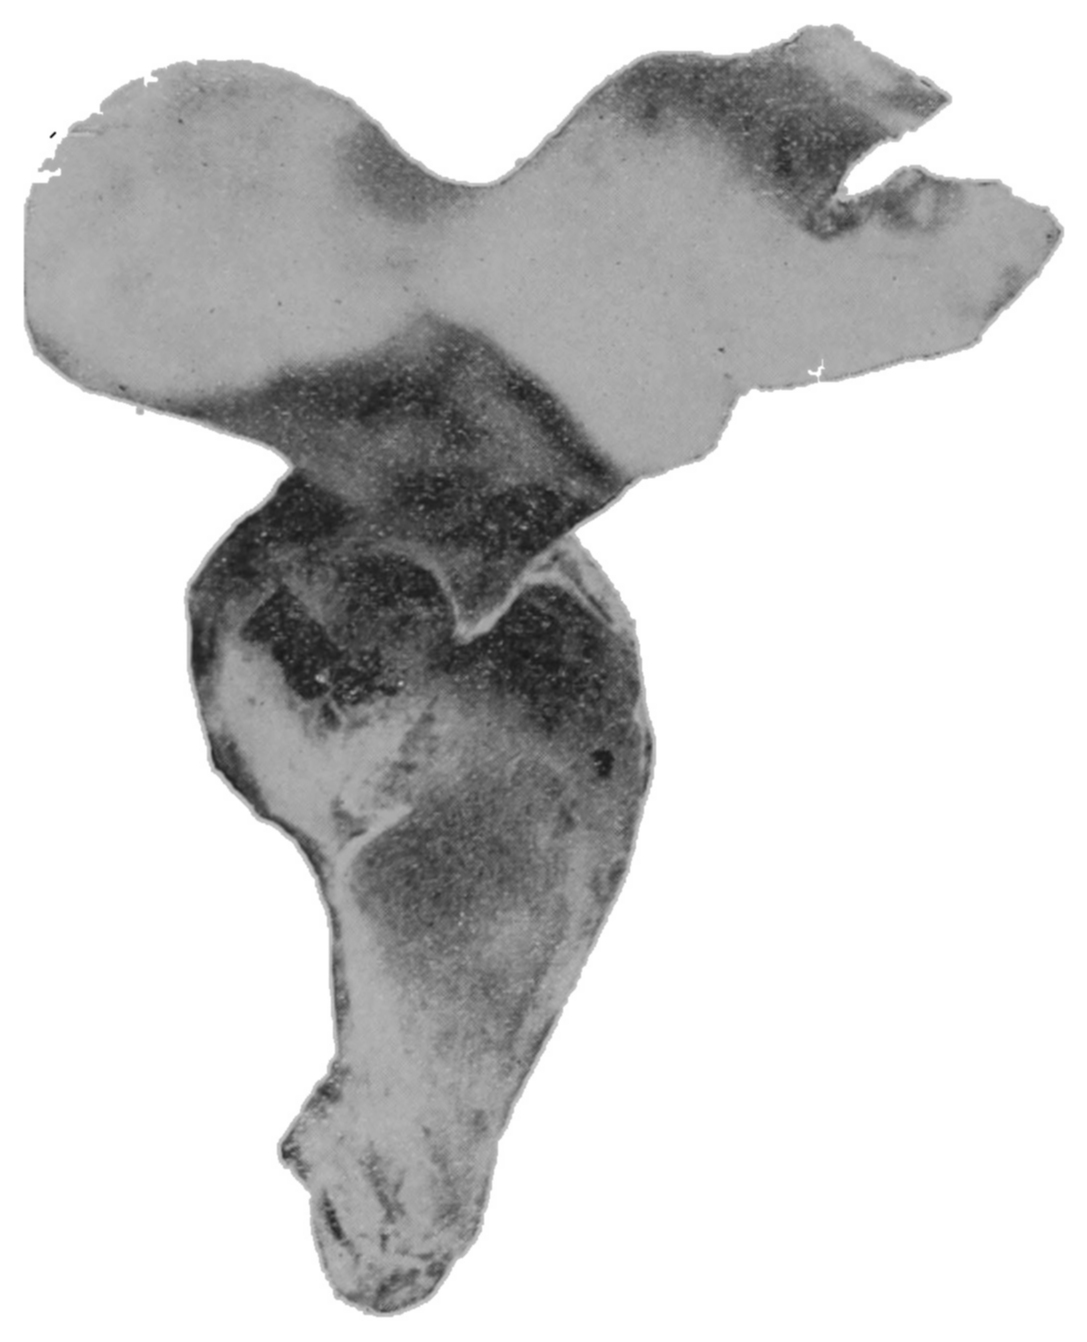

The photographic reproductions here published are documentary evidence of the existence of the obstructions under discussion. The sketch, Fig. 33, which was drawn from the valve while under the microscopic lens, exhibits the character of these obstructions and proves it that of a typic anatomic valve, and the absence of permanent bands of any other character in this organ is evidence that the semilunar valves and the so-called plica transversalis recti, Falten des Rectums, sphincter ani tertius, superior sphincter, and detrusor fecium muscles are one and the same thing and this thing is essentially a valve. It is most prominent when the gut is most distended.

Fig. 19.—Drawing of specimen No. 281 in the Anatomical Museum of the Royal College of Surgeons, London. The dissection was made by Mr. William Pearson. The drawing shows in the lower part of the field the coccyx, in the upper part of the field the pubes.

Fig. 20.—Drawing of specimen No. 284 in the Anatomical Museum of the Royal College of Surgeons, London. The dissection was made by Mr. William Pearson. The drawing shows in the lower part of the field behind the rectum the coccyx, in the upper part of the field the pubes.